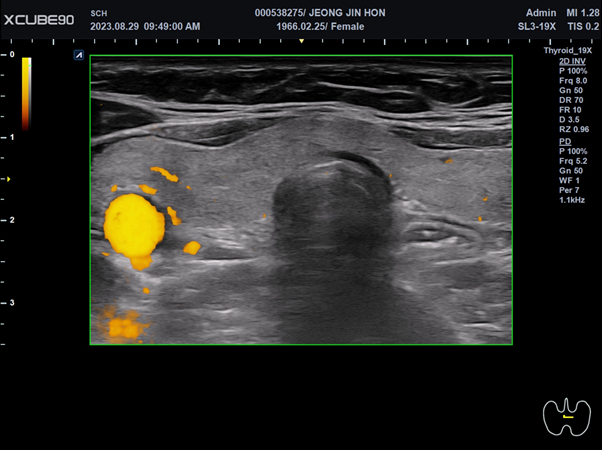

도플러 모드는 고정된 관측자 쪽으로 음원이 이동하면 주파수가 증가하고 멀어지면 주파수가 감소하는 도플러 효과에 근거한 이미징(imaging)방법으로 관측자는 탐촉자가 되겠고 반사체는 적혈구가 되어 음원을 발생하는 탐촉자 쪽으로 혈류가 가까워질 때 탐촉자에서 수신되는 반사주파수가 증가되고 혈류가 멀어지면 반대로 반사주파수가 감소하게 된다. 도플러 모드에서는 혈류가 탐촉자 방향을 향하게 되면 빨간색으로, 멀어지면 파란색으로 표현한다. Power doppler법은 방향성과 속도에 관계없이 도플러 신호의 강도를 민감하게 표시할 수 있는 방법으로 방향성과 속도는 알 수 없지만 적고 느린 혈류도 표시할 수 있는 장점이 있다. 도플러 모드를 사용 시에 불필요한 신호와 허상이 많이 나타나면 감도(gain)를 낮춰서 이를 감소시킬 수 있다.

그림 2. 도플러 모드 영상. 갑상선의 도플러 모드 영상.